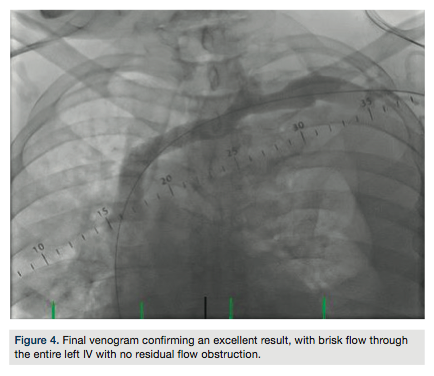

balloon, and then a 10.0 x 60 mm Mustang balloon, with good expansion. A Protégé 14 x 80 mm self-expanding stent (Covidien) was then deployed in the left IV and post-dilated with a 12.0 x 40 mm Mustang balloon. Final venogram confirmed an excellent result, with brisk flow through the entire left IV and no residual flow obstruction (Figure 4). Intravascular ultrasound imaging of the stented segment confirmed adequate stent apposition and expansion (Figure 5). Hemostasis was achieved in bilateral access sites with manual compression and the left upper extremity wrapped in compression bandages (Figure 6). The patient was subsequently transferred back to the original facility for management of his post-procedural care.